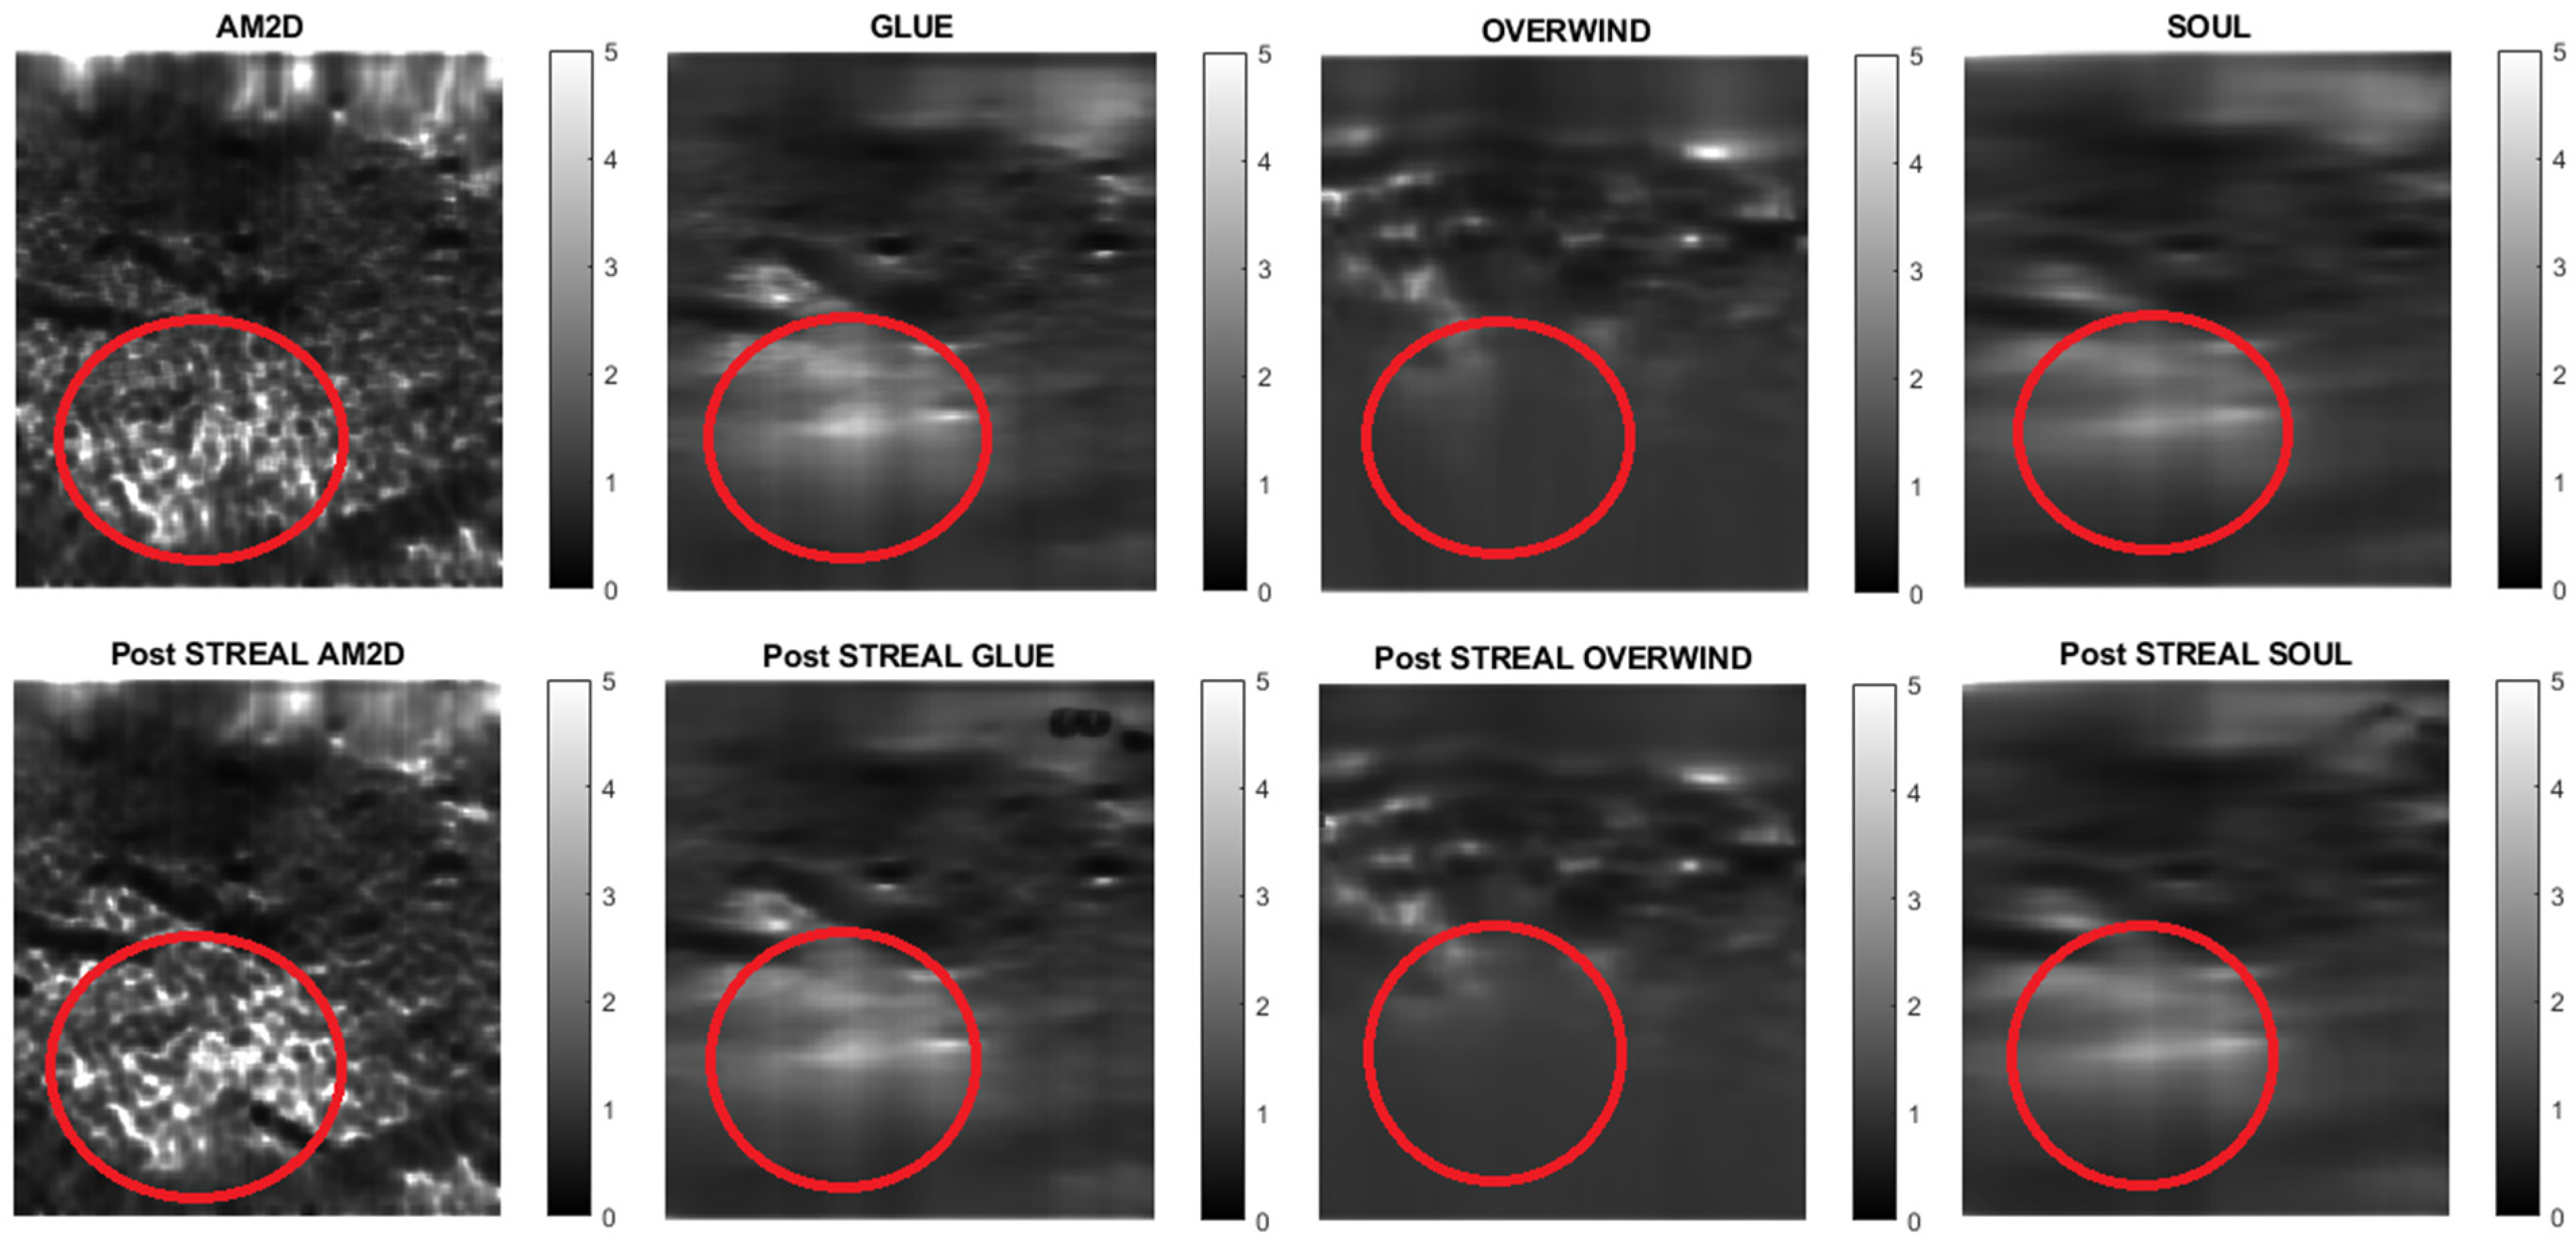

| AM2D | Analytic Minimization in 2-Dimensions |

| GLUE | Global Ultrasound Elastography |

| OVERWIND | tOtal Variational Regularization and WINDow-based time delay estimation |

| SOUL | Second-Order Ultrasound Elastography |

| STREAL | STrain Enhancement ALgorithm |